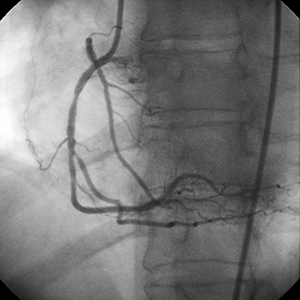

Diagnóstico

• La angiografía inicial no mostró una enfermedad significativa del sistema coronario izquierdo.

• La arteria coronaria derecha (RCA) presentaba un alto grado de estenosis con un segmento proximal prolongado de enfermedad.

• La función ventricular izquierdo era normal.

Procedimiento

• No se advirtió una calcificación significativa en el momento de la intervención (especialmente en la región del estrechamiento más crítico).

• Se implantó un stent de 2,75 mm × 23 mm.

• La angiografía demostró un implante no óptimo del stent debido a calcio no observado en la parte proximal de la lesión.

Posdilatación

• Se usaron balones de alta presión de 3,5 mm y 4 mm para postdilatar el stent.

• Los balones de alta presión no tuvieron éxito en la optimización de la expansión del stent.